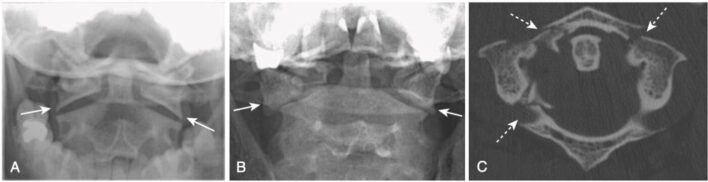

- Gãy Jefferson là gãy C1 thường liên quan đến cả cung trước và cung sau. Trong gãy kiểu cổ điển của nó, có gãy xương hai bên của cả cung trước và cung sau của C1, tạo ra cả thảy bốn vị trí gãy xương.

- Nguyên nhân là do chấn thương do lực tải dọc trục (ví dụ như nhảy xuống bể bơi và đập đầu xuống đáy).

- Trên phim chụp X quang thường quy, dấu hiệu của gãy Jefferson là lệch bù ra ngoài hai bên của các khối bên của C1 so với C2 quan sát được trên phim X quang cột sống cổ tư thế thẳng và há/mở miệng (open-mouth view) (góc nhìn đội trục). Gãy xương được khẳng định bằng chụp CT (Hình 15).

- Gãy xương Jefferson là gãy xương “tự giảm áp” (self-decompressing), trong đó ống sống ở ngang mức gãy xương đủ rộng để dung chứa bất kỳ sự sưng phù nào của tuỷ sống. Thường không có khiếm khuyết thần kinh liên quan đến loại gãy xương này.